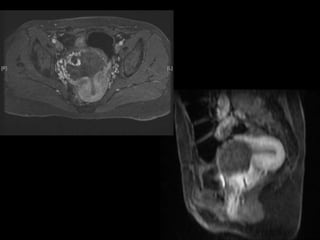

Dr. Hedvig Hricak

HISTORY

•   42 yo female

•   Recent immigrant from China

•   C/O postcoital and intermenstrual bleeding

•   Abnormal GYN exam

•   Abnormal biopsy

•   Further imaging performed

• What is the diagnosis?

• Staging?